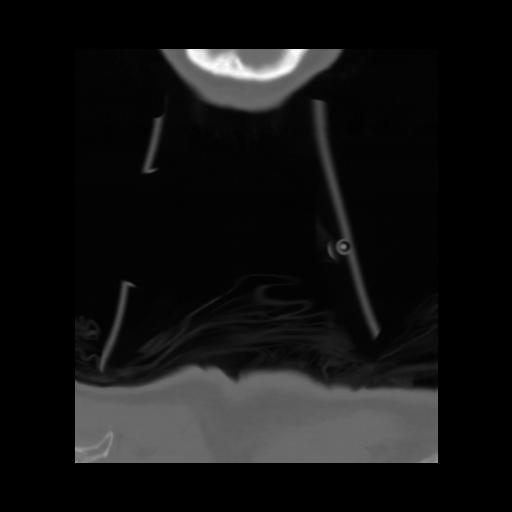

13 P.BLANDAS,,Coronal,2.000,P.BLANDAS,Coronal,